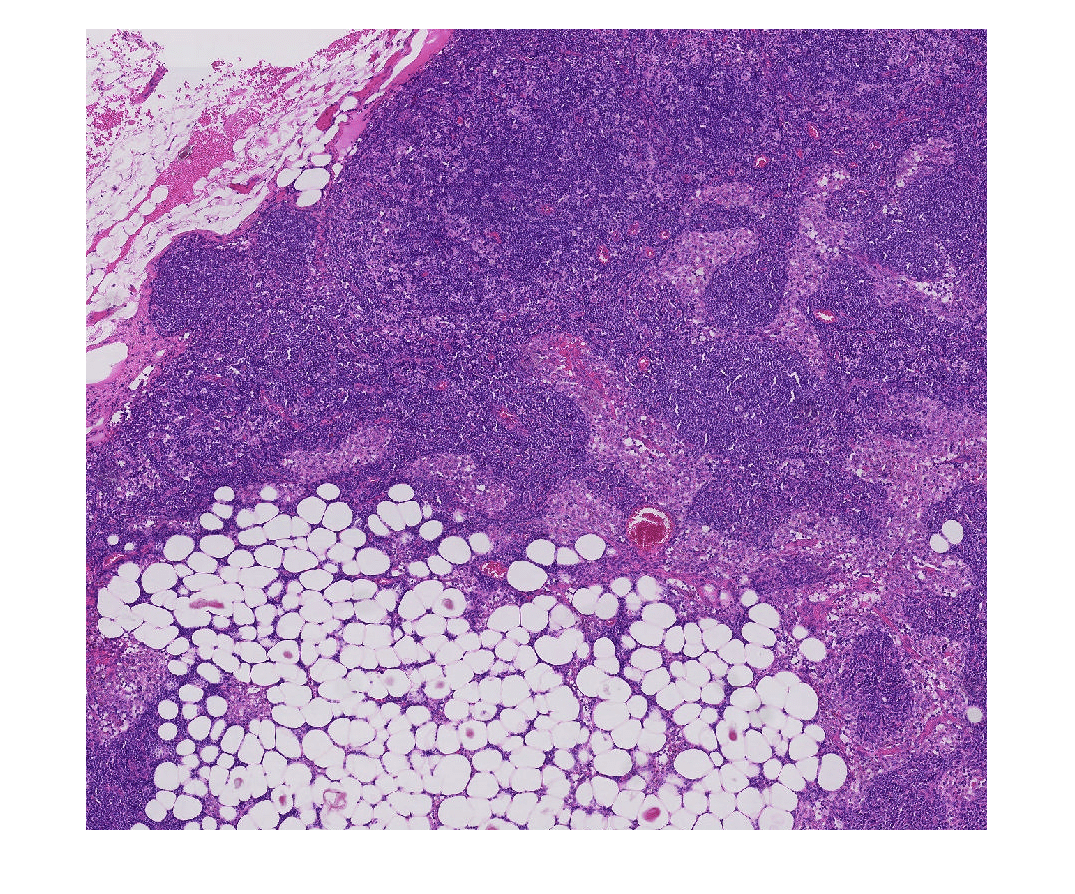

Создайте blockedImage объект с помощью модифицированной версии изображения "tumor_091.tif" от набора данных CAMELYON16. Оригинальное изображение является учебным изображением лимфатического узла, содержащего ткань опухоли. Оригинальное изображение имеет восемь уровней разрешения, и самый прекрасный уровень имеет разрешение 53760 61440. Модифицированное изображение имеет только три крупных уровня разрешения. Пространственная ссылка модифицированного изображения была настроена, чтобы осуществить сопоставимое соотношение сторон и указать функции на каждом уровне.

Отобразите блокированное изображение при помощи bigimageshow функция.

bigimageshow(bim);